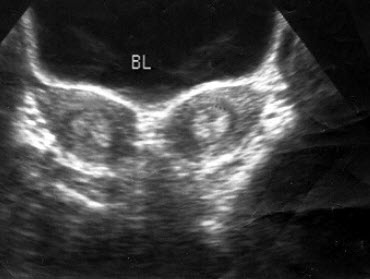

下图为宫内孕囊声像图,可见心管搏动,该胎儿至少大于多少周()